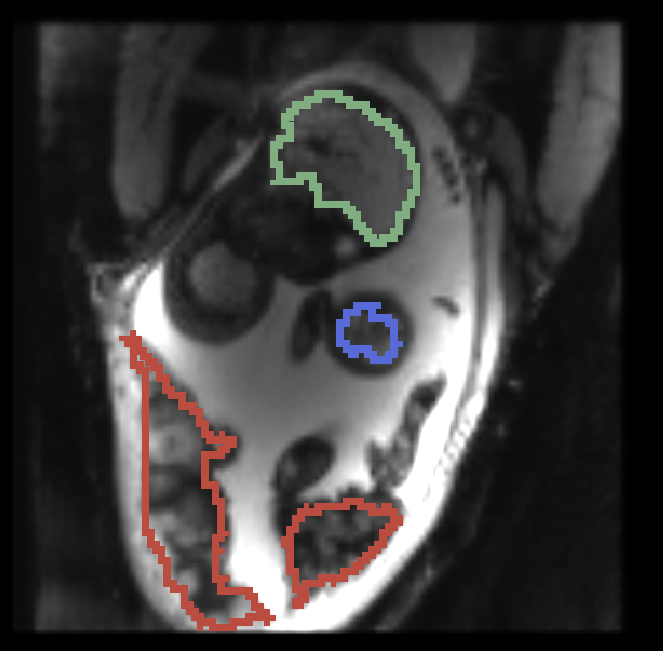

, manual segmentation on , manual segmentation on , propagated segmentation

Fig. 3 provides example results from the study for fetal brains and placentae. We observe that the reference frame is warped accurately by the temporal registration algorithm in the regions of fetal brains and placentae to represent the first frame in the series that is substantially different from the template. The delineations achieved by transferring manual segmentation labels from the reference frame to the coordinate system of the selected frame are in good alignment with the manual segmentation outlines for that selected frame.